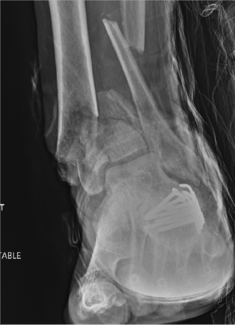

Shane Sato, DPM; Michael H. Theodoulou, DPM, FACFAS

The hexapod frame is a valuable tool in the foot and ankle surgeon’s armamentarium when used to correct the Charcot foot deformity in either an acute or gradual manner. There are multiple benefits if done acutely, less reliance on patient...